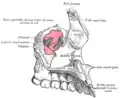

Maxilas em verde. Vista lateral.

Maxilas em verde. Vista lateral. -